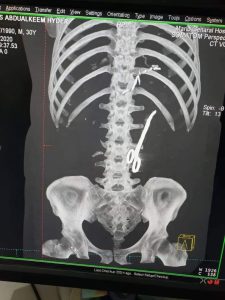

وأظهرت صورأشعة رنين مغناطيسي، لأحد جرحى قوات التحالف في محافظة مأرب، بأن الأطباء في مستشفى الهيئة المدينة، نسوا مقص جراحي، داخل بطن المجند “أنس حيدر” بعد إجراء العملية الجراحية، نتيجة إصابته أثناء المواجهات في اطراف مدينة مأرب.

وأرجع الناشطون، بأن كثرت الأخطاء الطبية التي ترتكب في مستشفيات مدينة مأرب تأتي لحالة الارتباك والأعياء التي يعاني منها الأطباء جراء الأعداد الكبيرة من الجرحى في صفوف قوات التحالف، ضمن الخسائر البشرية التي يتلقونها في أطراف مدينة مأرب.